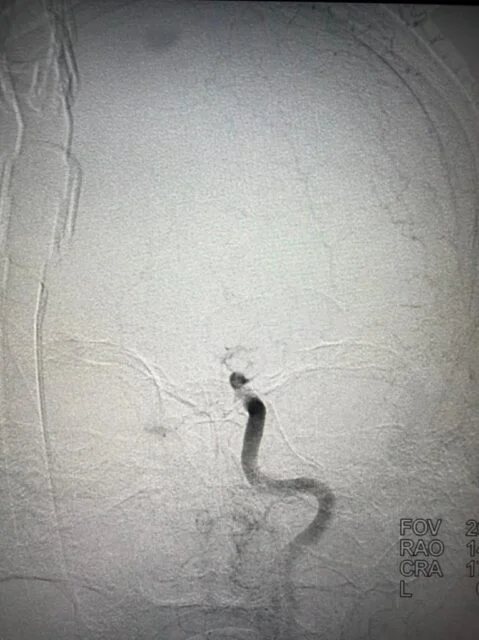

Successful Mechanical Thrombectomy in a relatively young stroke patient at ACCORD SUPERSPECIALITY HOSPITAL - A new hope for a large vessel stroke.